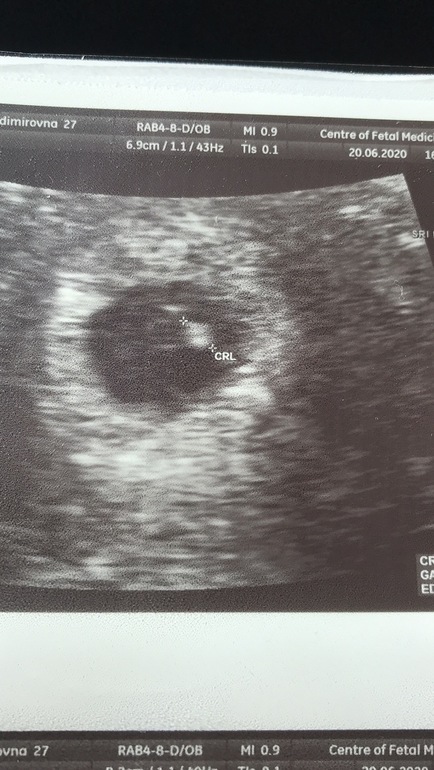

Первое узи , 23 ДПП

Затем попробовали на животе и все сразу как на картинке видно, она не успела даже сказать ничего, я сама уже увидела и мешочек и эмбриончик. Странно, но муж тоже понял что к чему 🤔, сжал руку так, что я невольно уже смотрела не на экран, а на него. Он такой напряженный, глаза на мокром месте. Узитка показала как пульсирует сердечко. Слева от меня уже какие то судорожные вздохи пошли. Я вместо того , чтобы самой всплакнуть, переживаю за мужа. Стали пробовать послушать сердечко, насчитали 109 у/сек. Знаю, что разгонется ещё. Вышли спокойные , оплатили. Только за порог, я как зареву крокодильими слезами! Так всю дорогу и ревела.